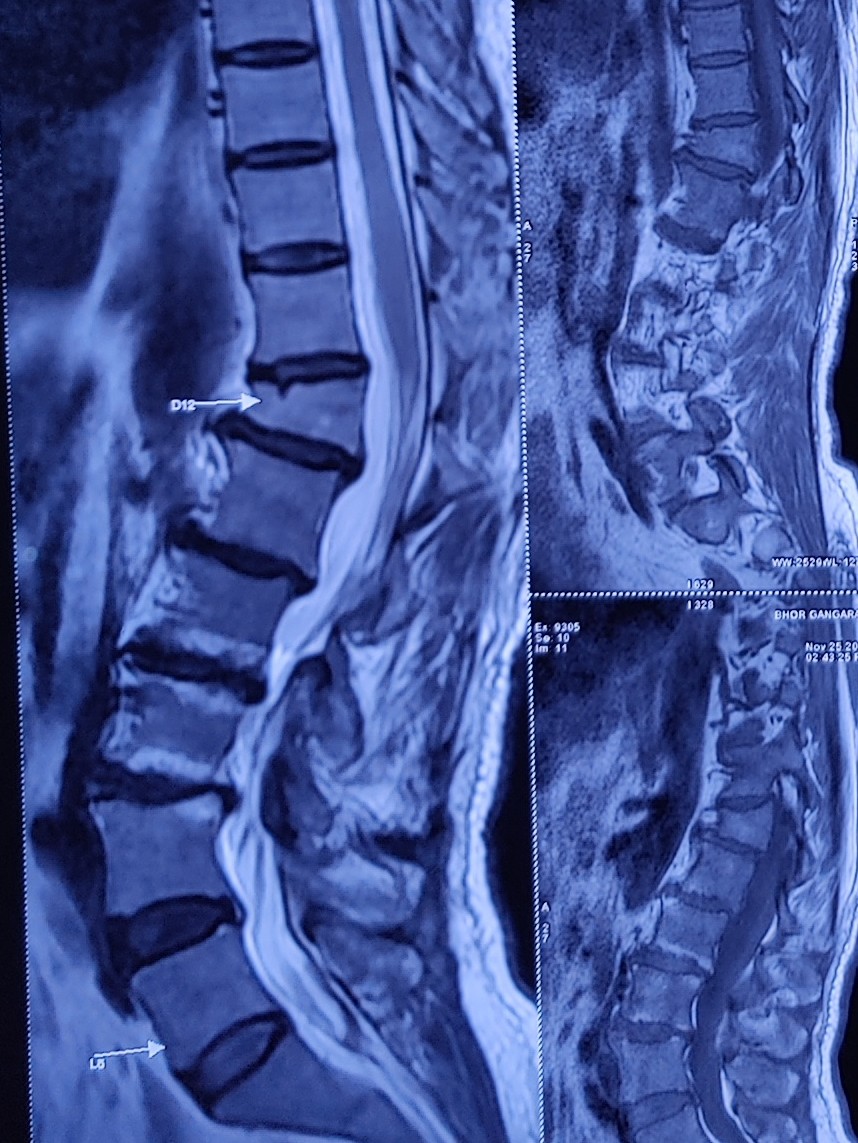

Vertebral compression fractures are one of the causes for the Severe acute onset Back pain. These fractures occur secondary to either injury, Osteoporosis or Metastatic lesions in the vertebrae.

Vertebroplasty is a minimally invasive procedure targeted to stabilize the fractured segment and reduce pain.

If there is significant reduction in the height of the vertebral body due to the fracture, we do a slight modification in this procedure which is then called as Kyphoplasty. Kyphoplasty involves first placement of a balloon in the fractured vertebral body through the needles and then injection of the cement into the balloon which not only stabilizes the fractured segment but also augments the vertebral body height.